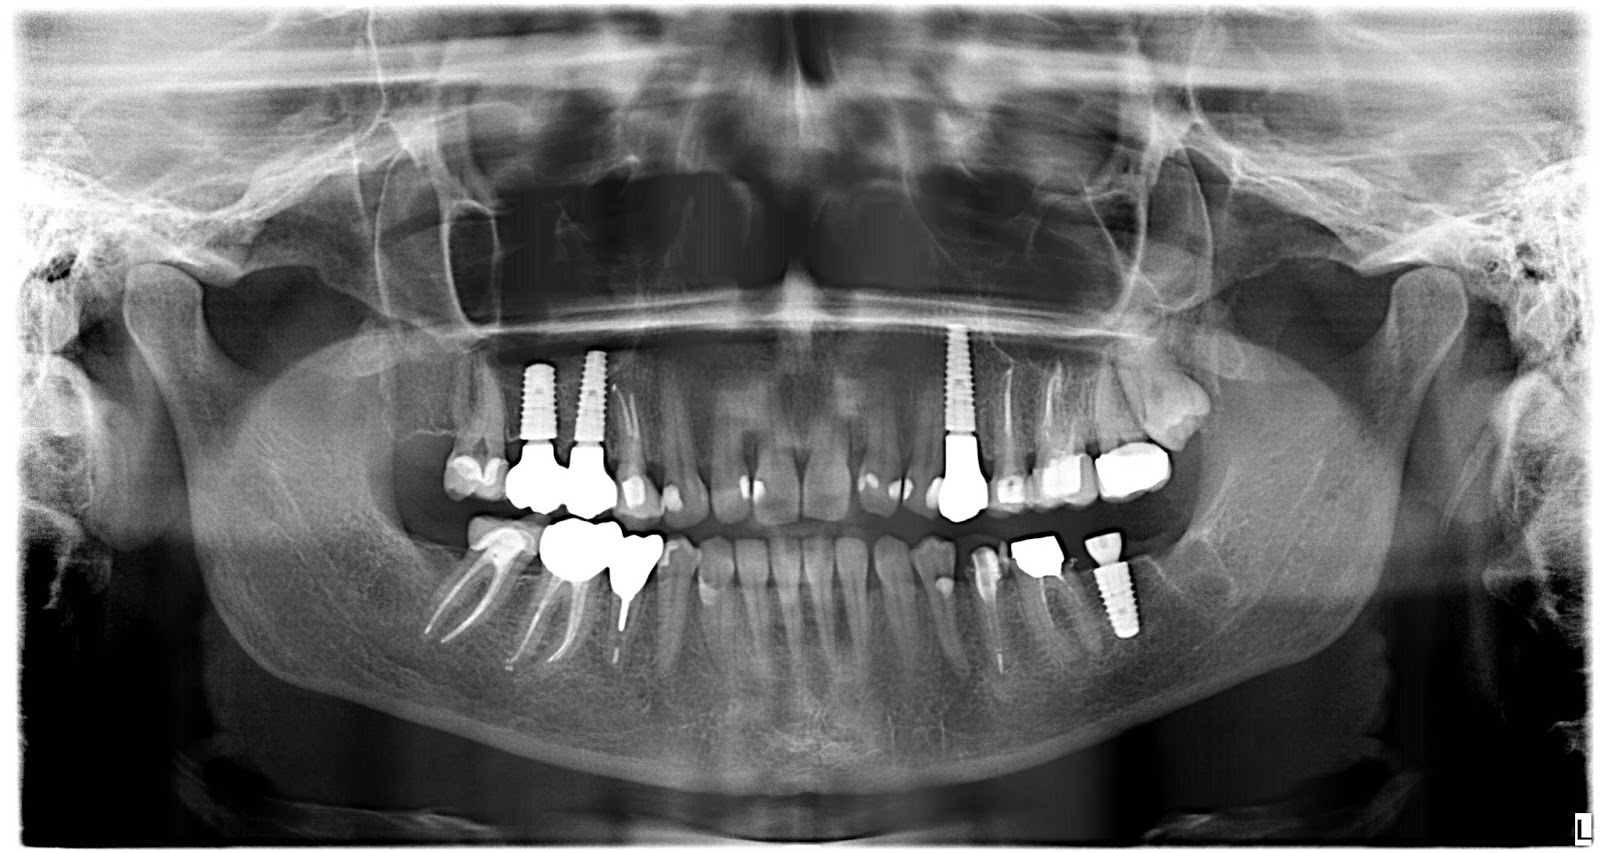

Tak tohle je mé intraorální já.

Pomalu zakončuju svoji dva a půl roku trvající stomatologickou misi. Řekla bych, že jsem v zubařském křesle strávila nějakou tu stovku hodin. Jen tenhle týden v pondělí pět a dnes dvě hodiny.

Sice bych za ty peníze měla asi notebook ze zlata, jenže genetika naší rodiny (co se zubů týče) je hodně neúprosná. A psát se dá přinejhorším i propiskou.

To je tema, ktere zrovna resim- implantaty a doplneni kosti.. Nechtelo by se vam napsat vic, na netu nejsou nici osobni zkusenosti… A zubare by jste mohla doporucit vim ze jste ho kdysi tady zminila, ale nepodarilo se mi to dohledat…. Dekuju a preju at zdravi pribyva☺